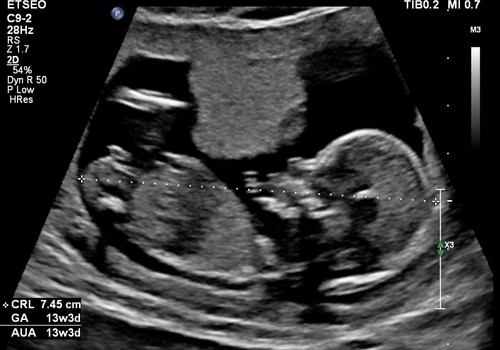

13 weken en 3 dagen

Helaas geen nub te zien